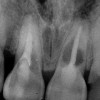

Figure 6  Excellent interproximal crestal bone level between the centrals before extraction.

Figure 6

Figure 10  In these adjacent implants placed in the central and lateral positions, note the excellent interproximal bone but minimal interimplant distance.

Figure 10